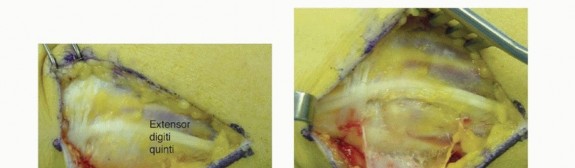

Open Reduction Distal Radioulnar Joint and Triangular Fibrocartilage Complex Open Repair Indicated in the treatment of the irreducible DRUJ following radial fixation If the DRUJ remains irreducible after anatomic reduction of the radial shaft fracture, soft tissue interposition is suspected. Open reduction to remove interposed soft tissue and TFCC repair should be performed.10 The following description assumes the native anatomy is not disrupted. Unfortunately, if this approach is being made for an irreducible DRUJ, there will be disrupted tissue planes as a result of interposed structures, capsular tears, etc. It is important to be able to identify the structures and attempt to restore them to their native positions, stabilizing them with tissue repair after joint reduction. A 2- to 3-cm gently curved dorsal longitudinal incision is made over the distal ulna, and blunt dissection is performed through the subcutaneous tissue, cauterizing small vessels with bipolar cautery (TECH FIG 2A). The dorsal cutaneous branch of the ulnar nerve is identified and care is taken throughout the procedure to protect it. A longitudinal incision is made through the thin extensor retinaculum between the fourth and fifth extensor compartments (TECH FIG 2B).3 Avoid amputating the flap during radial to ulnar elevation. Avoid violation of the ECU subsheath. The extensor digiti quinti (EDQ) is released from the fifth compartment and retracted radially. An ulnar-based capsulotomy is made (TECH FIG 2C). The distal transverse limb is made at the level of the palpable triquetrum, proceeding in an ulnar to radial direction along the dorsal radiocarpal ligament, from the ECU tendon to the floor of the fifth compartment. The capsulotomy is then continued proximally in a longitudinal fashion through the floor of the fifth compartment to the level of the ulnar neck. Care needs to be taken not to cut through the dorsal radioulnar ligament of the triangular fibrocartilage (TFC). Small double skin hooks placing tension on the capsular flap will assists in avoiding injury to the underlying TFC. Finally, the proximal transverse capsulotomy is made across the ulnar neck to ECU tendon. If needed for visualization and working space, the ulnomeniscal homolog, which extends distal from the TFC into the ulnocarpal joint, can be excised. Bipolar cautery may be needed for hemostasis following its excision.3 The key to the entire dissection is to create clean planes that sharply define the structures, allowing them to be repaired during layered closure. Next, a small curette is used to create a small trough in the ulna fovea exposing cancellous bone.

TECH FIG 2 • Open DRUJ/TFCC exposure and repair. A. Incision. B. Extensor retinaculum opened exposing fifth compartment. C. TFCC and DRUJ exposed. D. 3-0 nonabsorbable sutures placed through TFCC and ulna bone tunnels. E. Final construct demonstrating transfixation with 0.062-inch K-wires and TFCC repair. A 0.045-inch smooth stainless steel pin is used to drill two bone tunnels, separated by a 1-cm bony bridge, from the medial ulna to the ulnar fovea. Next, three 3-0 braided nonabsorbable suture are passed one at time through one of the bone tunnels, through the TFC, and back out the other bone tunnel (outside-in to inside-out) (TECH FIG 2D).9 Prior to tying the sutures, the DRUJ is reduced and pinned with two 1.6- or 2-mm smooth stainless steel pins as previously described. Finally, the sutures are tied down over the ulna. A layer-by-layer closure is performed. The dorsal radioulnar ligament of the TFC can be sutured back to the capsule during closure (TECH FIG 2E).